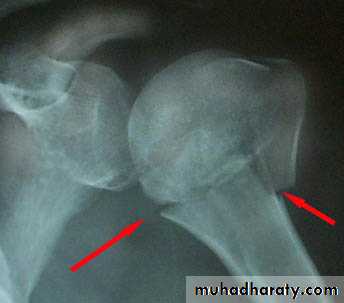

Posterior shoulder dislocation

It is rare less than 2% it occur due to marked internal rotation with adduction ; it occur inConvulsion or with electrical shock .

Clinically : the arm is held in medial rotation and it locked in that position .